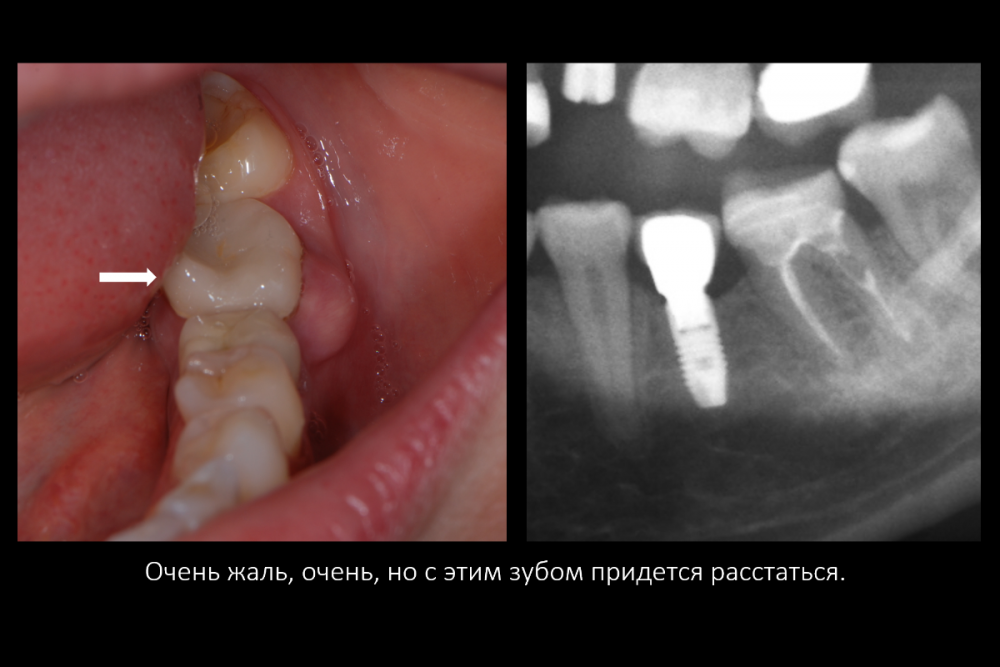

Карен Аванесов Опубликовано 16 июля, 2021 Поделиться Опубликовано 16 июля, 2021 Вариант герметизации послеоперационной раны, когда, хочется установить имплантат и сократить для пациента сроки реабилитации. Итак, "Астра" отличные имплантаты при хороших условиях работают, при экстремальных ситуациях выбор калибров сильно страдает и суживает возможности оператора (очевидно менеджерам не интересно будущее системы, эксклюзивная цацка профайл и маркетинговое продвижение на "озоне" это не то), как по мне, раздутый, абсолютно не удобный хирургический набор, не разделяю восторгов относительно эксклюзивности и предписуемым волшебным свойства, кость наросла! это только на "астре" так или только на анкилозе! На любой системе можно получать результаты. Представляю клинические случаи с одинаковыми условиями, но разными системами, там где "астра" не захотела первичной стабильности, в виду недостаточно широкой талии, "дентиум" диаметром 6мм встал бы на ура, но "астра" такой заказ ортопеда. 8 1 1 3 Ссылка на комментарий

Карен Аванесов Опубликовано 21 февраля, 2022 Автор Поделиться Опубликовано 21 февраля, 2022 Дозрела костна ткань. Возвращаясь к вопросу о "волшебстве" брендовых систем.... Безусловно, молодому специалисту, через сопливый нос бубнить на консультации что от СТАВИТ страуманн, мобель или аштру, поднимает самомнение, окрыляет, иногда и до звездной болезни, помогает быстрее "заматереть,"но сути не меняет. Кость "подрастает" не только аштре например, что иногда демонстрируют с восторгом, но и на отстойном дентиуме тоже, и думаю и на отстойной альфа-био и т.д., т.е. все-же от условий зависит, пациента и конечно техника, что там как и дальше будет. Соберу кейс покажу вошебный рост на голых витках корейского народного ширпотреба)))) 1 Ссылка на комментарий